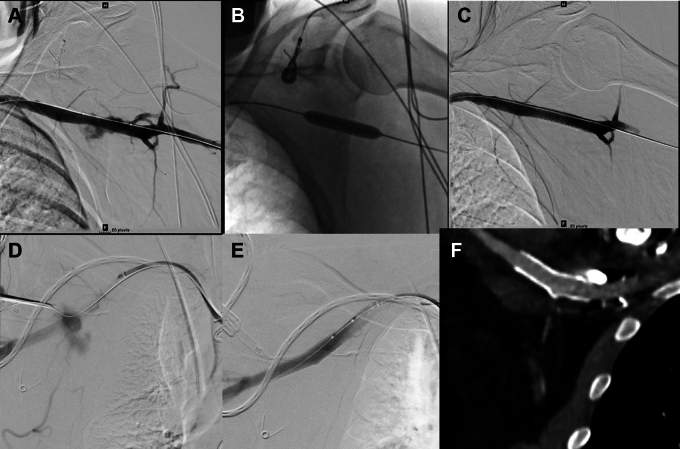

Figure 6.

Covered stent use for bleeding. A) Bleeding at axillary puncture site B) balloon inflation across the puncture site C) Stent graft bailout. D) Extravasation at axillary artery puncture site after Perclose closure failure. Angiogram performed while testing closure. Note maintenance of wire access at axillary puncture site and safety wire across axillary artery E) Hemostasis after deployment of self-expanding Viabahn (W.L. Gore) covered stent F) CTA at 1-month follow-up showing patent axillary artery covered stent.